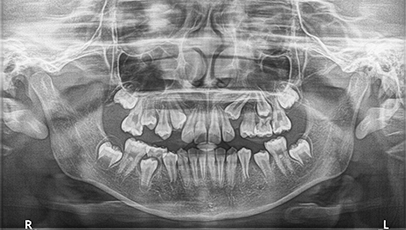

Before & After

아래 양쪽 끝 어금니가

적절한 교정치료후 똑바로 일어섰습니다